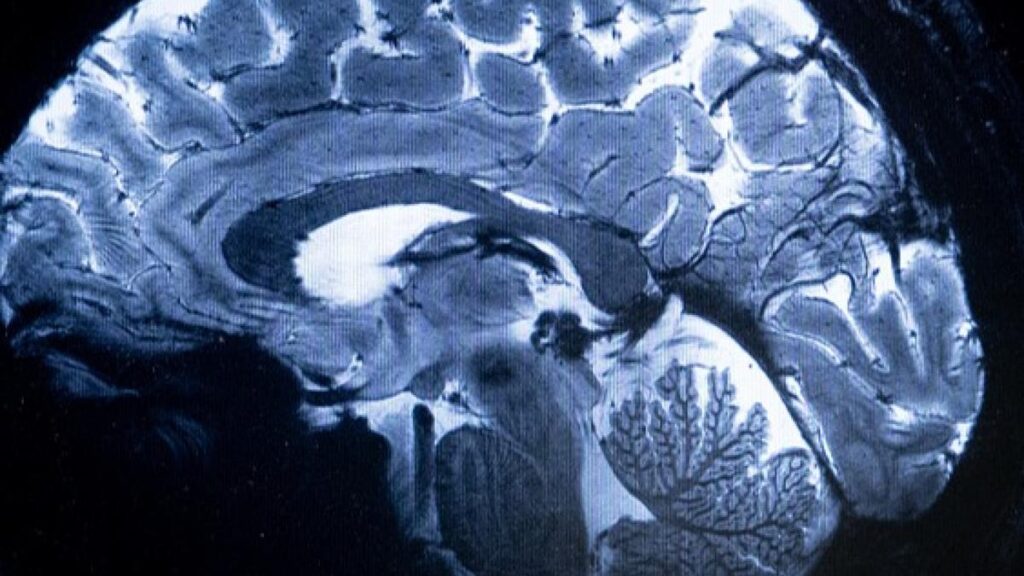

The comprehensive study tracked nearly 6,000 civil servants over a span of 25 years. Those who eventually developed dementia consistently exhibited higher troponin levels long before any symptoms appeared. Brain scans conducted later revealed that participants with elevated troponin also had smaller hippocampi—an essential brain region for memory—15 years after initial measurements.